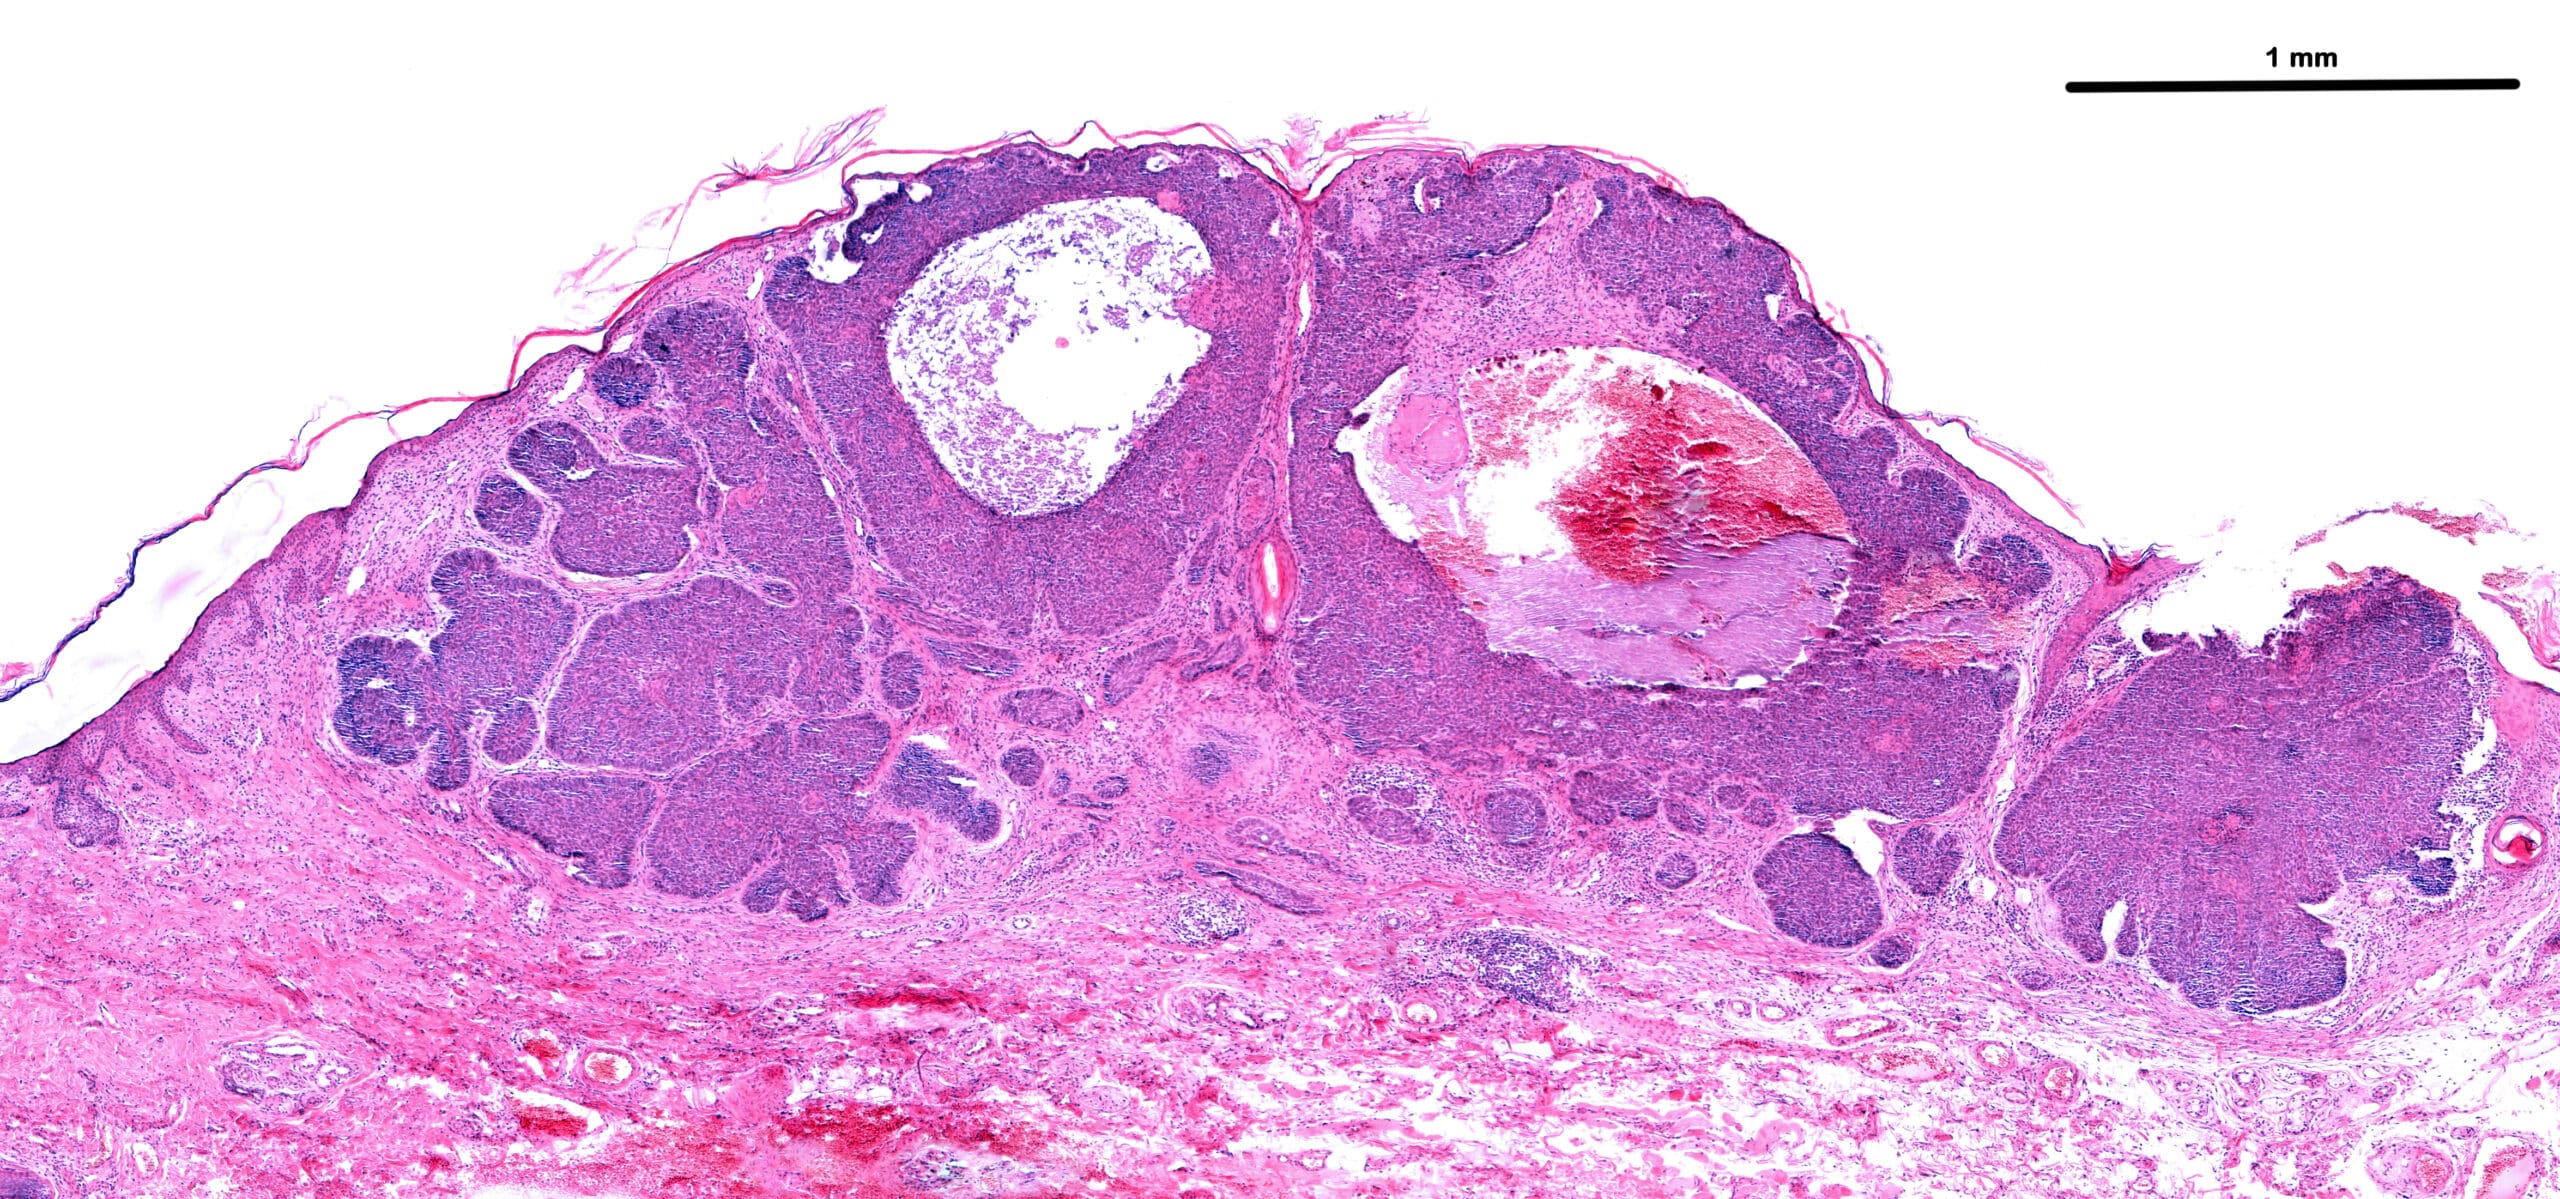

扁桃

画像質量細胞測定法(IMC)

1回のスライドから最大37個のタンパク質バイオマーカーを分析する。 HBRIの画像質量サイトメトリー(IMC)サービス。